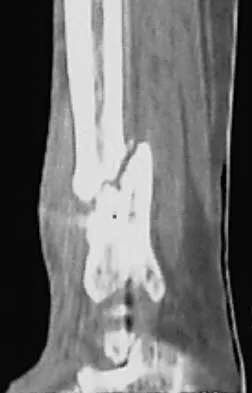

A 68-year-old woman who sustained a closed distal tibia fracture 2 years ago was initially treated with an external fixator across the ankle for 12 weeks, followed by intramedullary nailing of the fibula and lag screw fixation of the tibia. She continued to report persistent pain so she was treated with a brace and a bone stimulator. She now reports pain in her ankle. Examination reveals ankle range of motion of 8 degrees of dorsiflexion to 25 degrees of plantar flexion. She is neurovascularly intact. Current radiographs are shown in Figures 9a through 9c. What is the next most appropriate step in management?